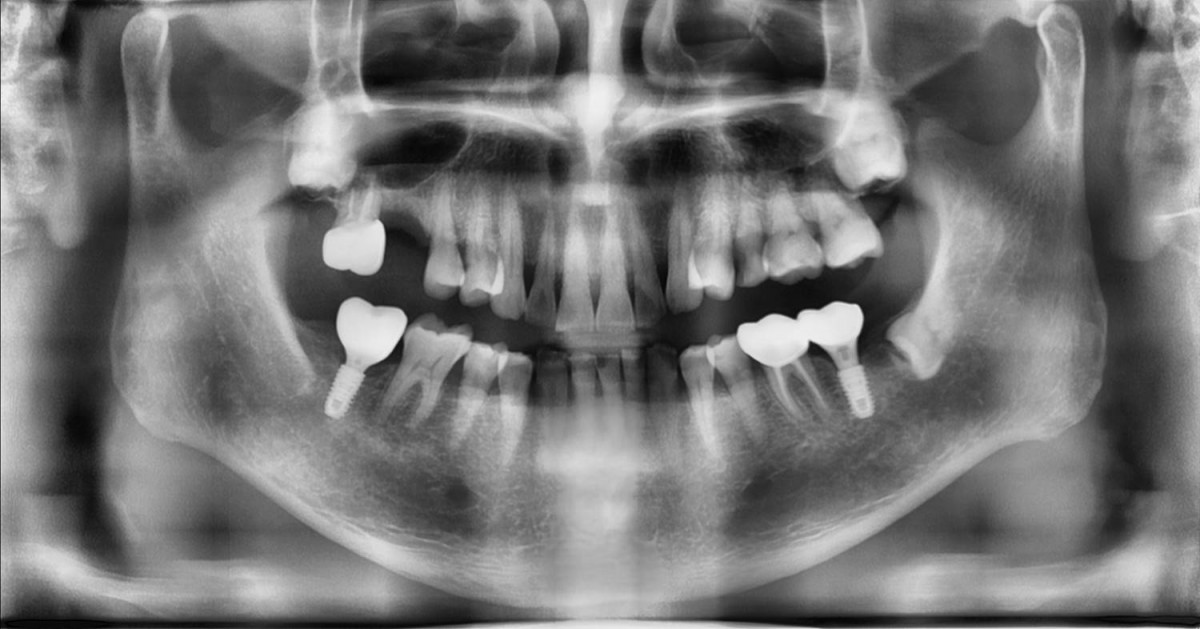

Maxillary Sinus Graft, 2 Implants, Crown Contouring

<GCaks> A 56-year-old male patient had pain-inducing caries, and perio-involved tooth mobility resulted in a tooth fracture at 1st molar. And it was removed months ago. He was a heavy smoker and showed poor oral hygiene.